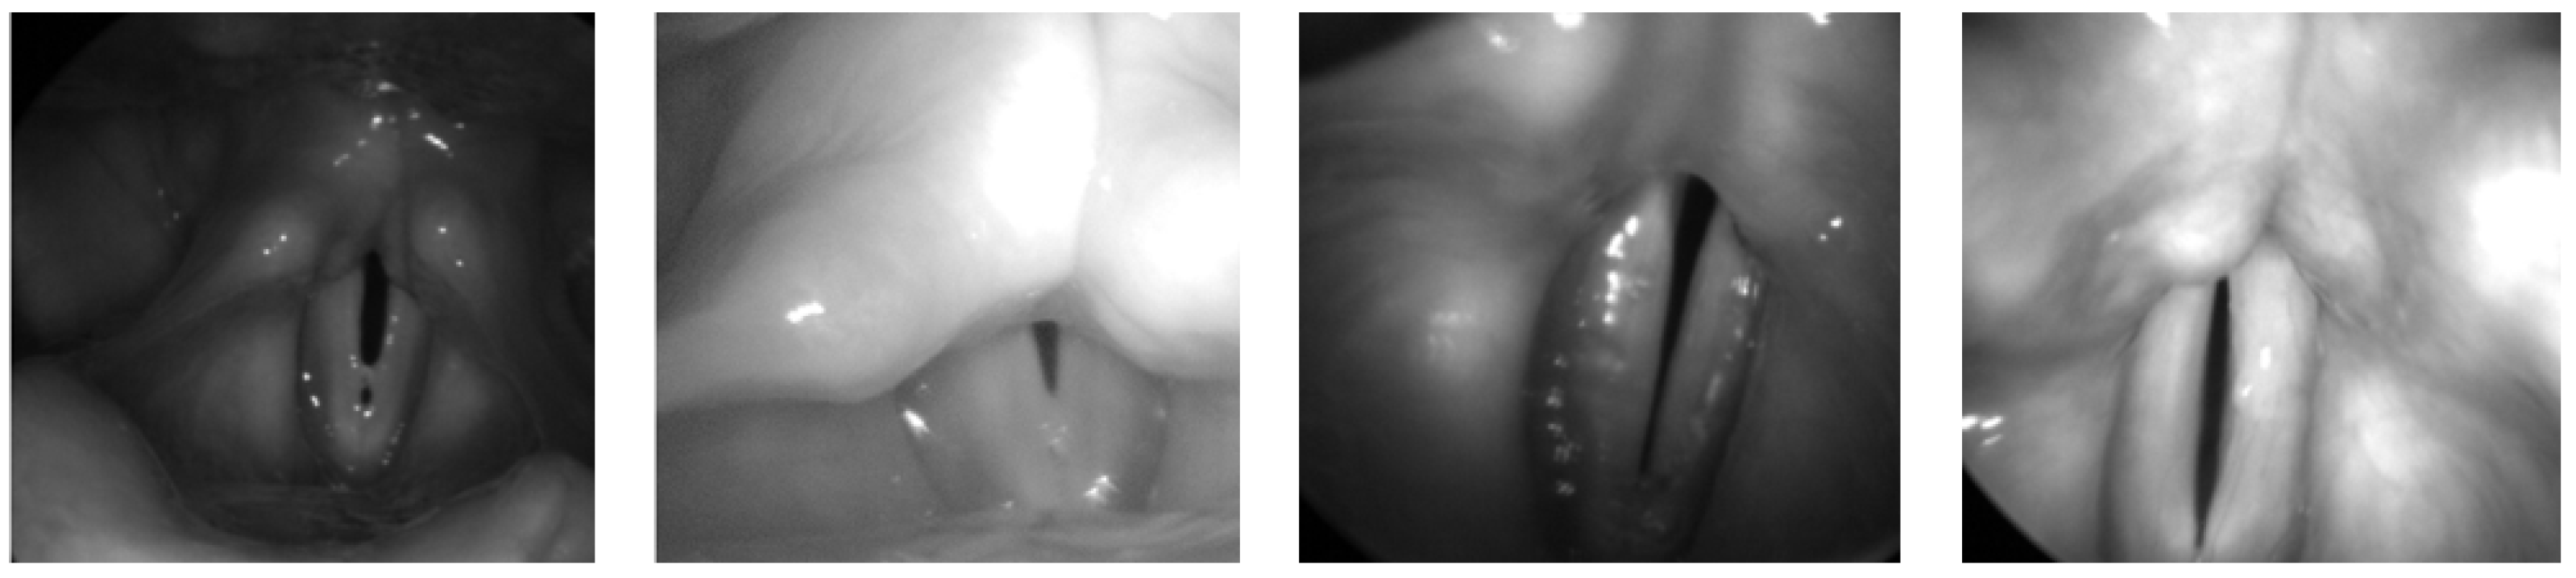

- Glottis: The Benchmark for Automatic Glottis Segmentation (BAGLS) [35] dataset comprises high-speed videoendoscopic recordings from 640 subjects, including both healthy individuals and patients with various laryngeal disorders. The data are collected by multiple medical professionals using diverse endoscopic systems, introducing substantial heterogeneity in image resolution, lighting conditions, and anatomical variations, as illustrated in Figure 5. To adapt this dataset for object detection tasks, we derive bounding boxes that tightly enclose the original segmentation masks and convert the annotations into the COCO [36] format. The resulting dataset includes 55,750 images for training and 3500 for testing. This large-scale and diverse dataset serves as a critical benchmark for evaluating the generalization capability and real-world applicability of our model across different patient groups and imaging devices.